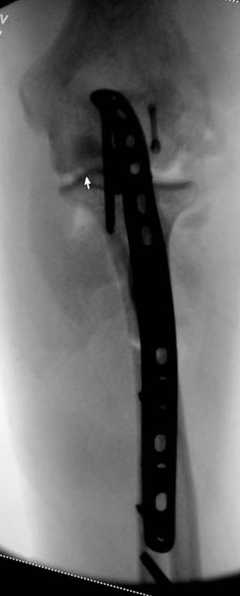

Для фиксации перелома локтевого отростка на сегодня множество преконтурных с блокирующими возможностями пластин.

Стабильную фиксацию, особенно при оскольчатых

переломах, можно добиться, применяя технику Bridge Plate, и за счет тех пластин, где имеется возможность проведения множественных шурупов (2.7 мм) проксимально.

Предложенные реконструктивные пластины в 3.5 мм

идеальны для фиксации при отрывном или флексионном

переломе, когда имеется большой фрагмент.

Здесь выставлены несколько случаев и варианты фиксации локтевого отростка, некоторые в комбинации с другими переломами.

3 вариант

перелом с capitelum humerus и проксимальной трети улна